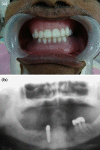

The conventional modality of treatment of partial edentulousness with reduced number of teeth was to render them complete edentulous and provide them complete denture or an overdenture with support of few remaining teeth. The goal of maintenance of roots are to prevent alveolar bone resorption, provide better load transmission, maintain sensory feedback and achieve better stability of denture with emphasis on psychological aspect of not being completely edentulous. Over the recent past titanium dental implants have been successfully used as tooth replacement with predictable results. A combination of tooth and implant support is well documented for fixed partial dentures but rarely for overdentures. This clinical report aims at evaluation of tooth root and implant supported mandibular overdenture treatment with telescopic coping.